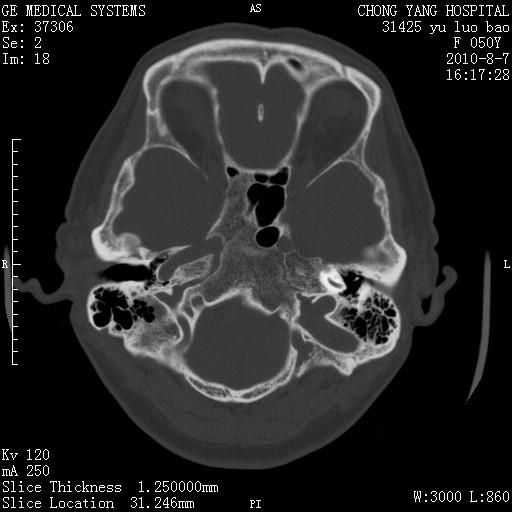

标题: CT28285:听力下降一年,头昏。 [打印本页]

标题: CT28285:听力下降一年,头昏。

右侧桥小脑角去等密度占位,右侧内听道扩大、骨质吸收,考虑:右侧听神经瘤,建议增强检查。

右侧内听道扩大、骨质吸收,中脑受压左移,考虑:右侧听神经瘤,建议增强检查。支持!

骨窗示右侧内听道扩大,考虑右侧听神经瘤。

右侧桥小脑角区等密度占位,内耳道扩大,听神经瘤